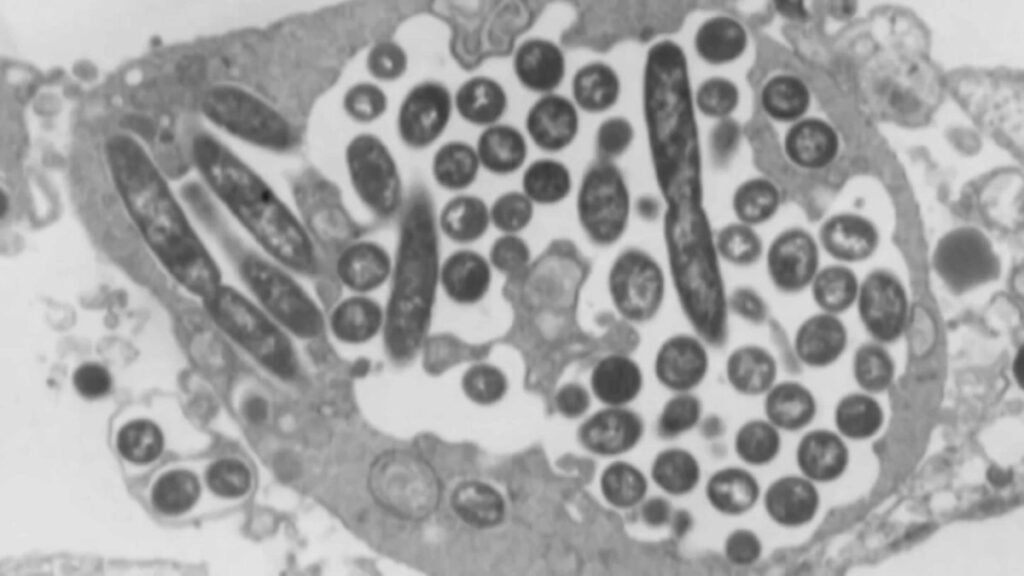

Legionnaires’ illness is a sort of pneumonia that’s brought on by Legionella micro organism, which grows in heat water and unfold via constructing water techniques.